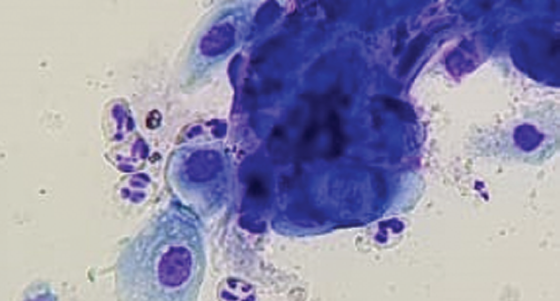

В группе больных, оперированных по поводу язвы роговицы после длительной противовоспалительной терапии, наблюдалась иная картина замещения эпителиального дефекта. В мазке-отпечатке у больного из этой группы на вторые сутки после операции определялось большое количество воспалительных клеток — нейтрофилов и лимфоцитов (рис. 2). Эпителиальные клетки имели округлую форму, были меньше по размеру, с более тёмной цитоплазмой и с большим количеством включений. Наличие клеток с тёмной цитоплазмой и большим количеством включений объясняется активностью воспалительных процессов. Активные клетки продуцируют матриксные металлопротеиназы, приводящие к лизису базальной мембраны и расщеплению межклеточных связей и, как следствие, к десквамации целых пластов эпителиальных клеток. Однако в зоне дефекта эпителия десквамированные эпителиальные клетки не могут фиксироваться на поверхности трансплантата в силу продолжающейся активности матриксных металлопротеиназ [9, 10].

Рис. 2. Пациентка Р. Диагноз: «OS — язва роговицы. Вторые сутки после сквозной кератопластики». Окраска Лейкодиф 200 (LDF 200). Увеличение ×400

Fig. 2. Patient R. Diagnosis: Corneal ulcer of the left eye. Second day after penetrating keratoplasty. Leucodif 200 (LDF 200) stain. Magnification ×400